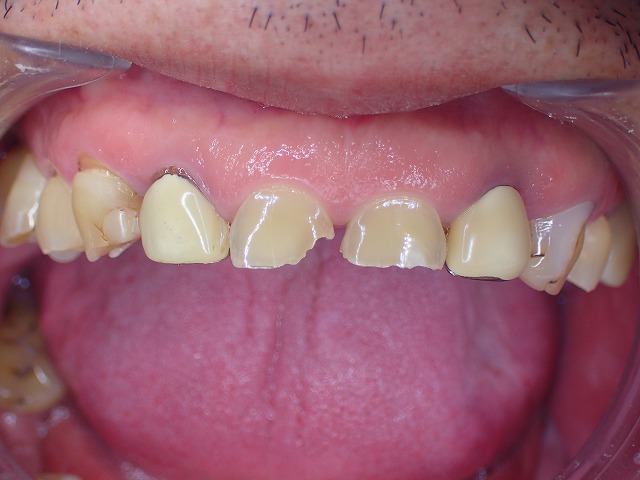

歯ぎしりが強く、前歯が極度にすり減ってしまった患者さんのケースです。

前歯はすでに割れ始めており、この状態でレジン充填を行うと、先端からさらに崩壊が進む可能性が高いと考えられます。

激しい歯ぎしりによって前歯が極度に摩耗し、割れ始めている症例です。

歯ぎしりによって歯が割れています。

裏側から エナメル質が完全に消失しています。

銀歯の先端も大きく摩耗しています。